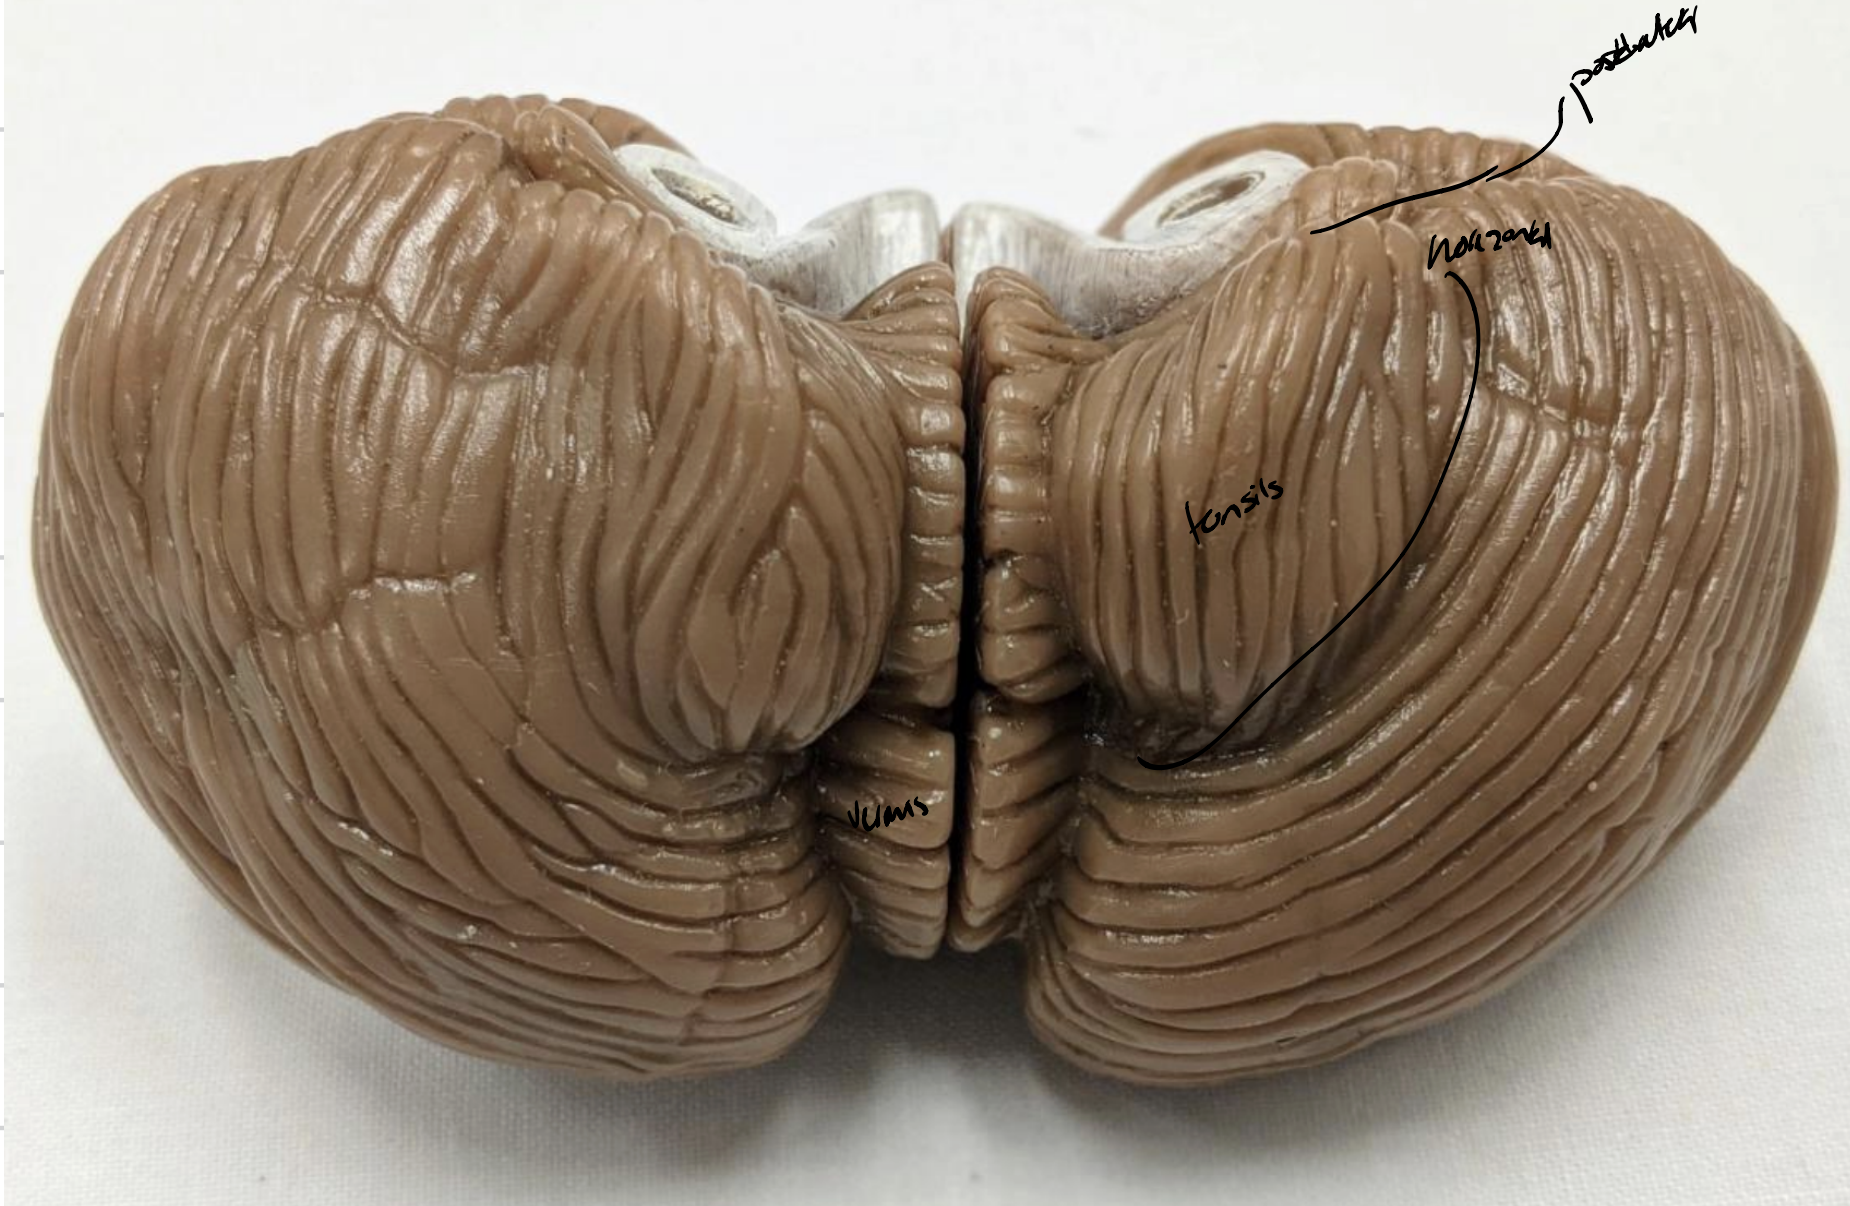

Cerebellum

Anterior lobe of cerebellum

Horizontal fissure

Posterior lobe of cerebellum

Cerebellar tonsils

Posterolateral fissure

Superior medullary velum

Arbor vitae

Folia